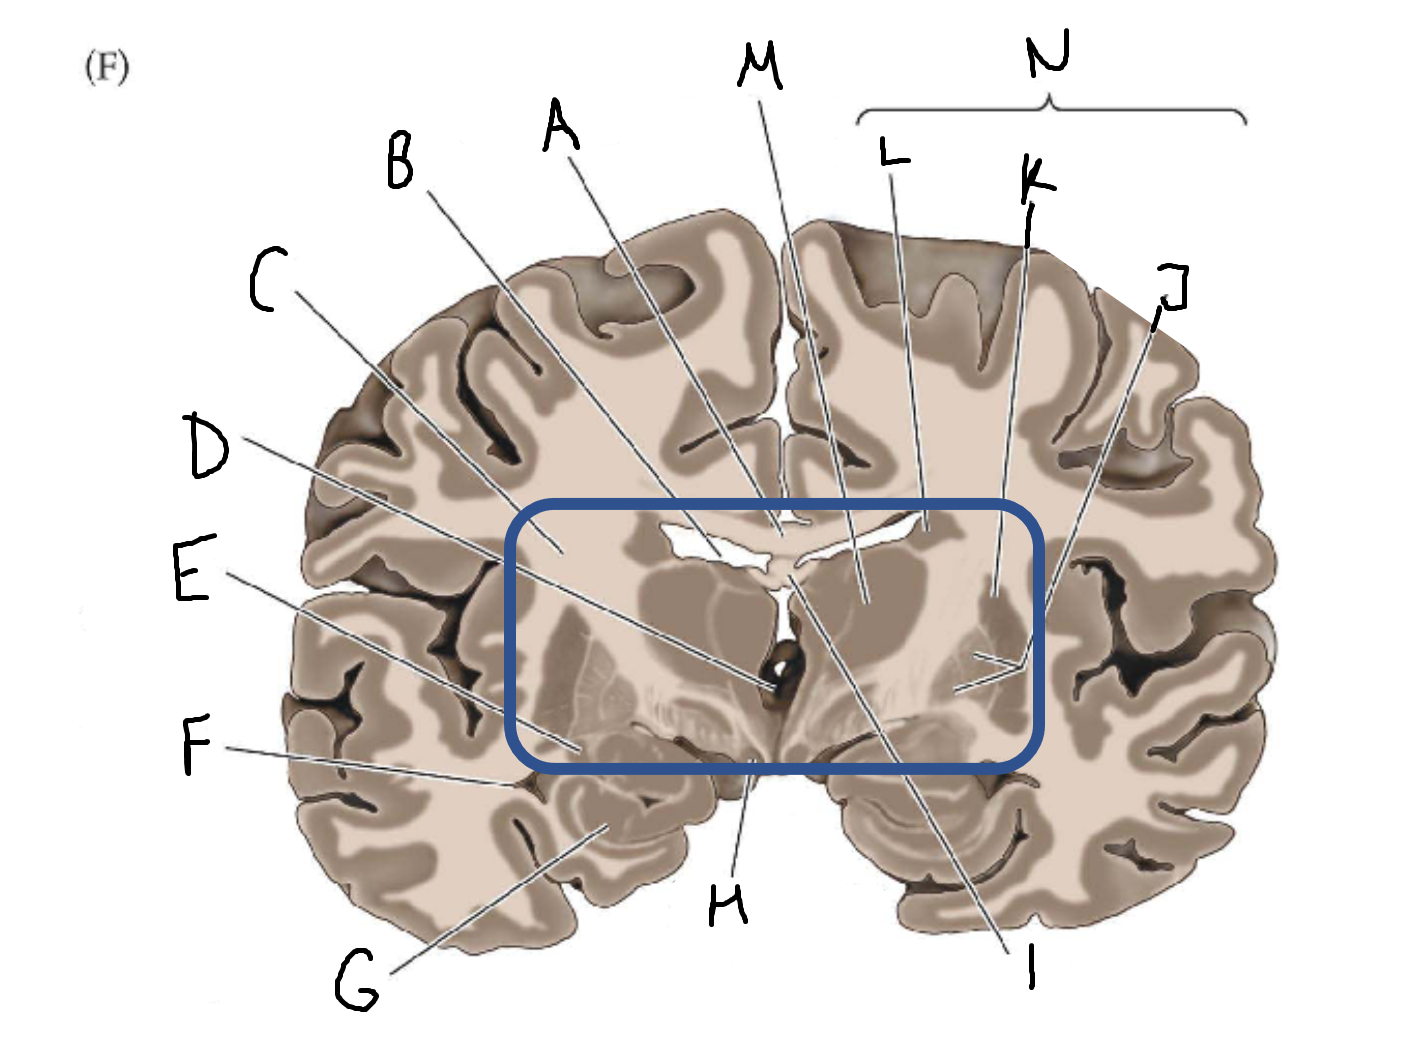

A

corpus callosum

B

lateral ventricle

C

internal capsule

D

third ventricle

E

tail of caudate nucleus

F

lateral ventricle

G

hippocampus

H

mammillary body

I

fornix

J

globus pallidus

K

putamen

L

caudate

M

thalamus

N

basal ganglia